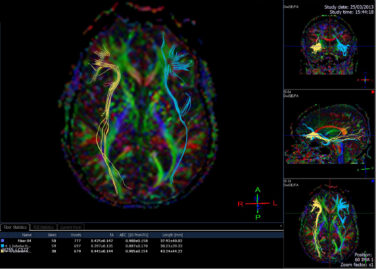

Rewiring the Brain: A Hopeful Path for Children with Dyslexia